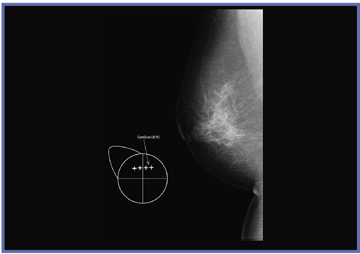

当初は,画像上に重ねてマーカーを入れていたが,読影する医師に先入観を与える可能性があるという指摘があった。そこで,医師に新しいマーカーを考案してもらい,メーカーに作成してもらった(図1)。具体的には,乳房の領域を示すモデル(a)と,画像上でそのまま大きさを比較できるように大きさを5mm(b),10mm(c)とした,ほくろやいぼを示すマーカー,手術瘢痕の形状を示すための5mmの十字マーカー(d)である。当センターではこれらのマーカーを使用することにした(サイズは実寸表示した場合の大きさ)。

図2は,ほくろの入力例である。右A領域にほくろがあったことがマーカーで示されており,画像上に認められる結節がほくろと一致するかを,読影医が判断することができる。図3は,いぼの入力例である。これまでは,コメントを記載するだけで,詳細な大きさや位置を伝えられずにいたが,マーカーの使用により,視覚的な判断が容易となる。また,図4は手術瘢痕の入力例である。以前は構築の乱れに合わせて画像上にマーカーを重ねていたが,新しいマーカーを使用することで,読影医は先入観を持たずに観察でき,技師の示した所見は参考情報として考慮することができるようになった。十字マーカーは1つずつ入力可能なため,直線や円弧状,乳輪に沿った形など自由に記載でき,ニュアンスを伝えやすい。